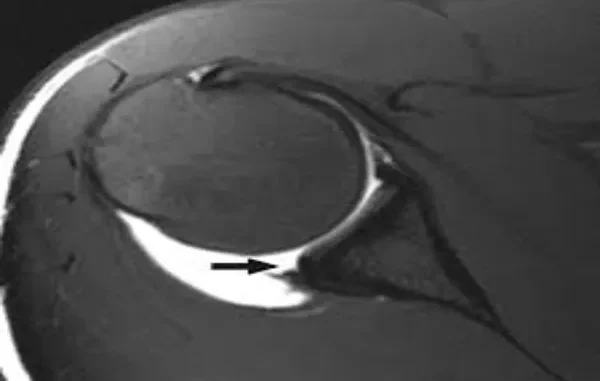

Magnetic Resonance Imaging (MRI) allows doctors to see the soft tissues of your shoulder in detail, something standard X-rays cannot do. Since the labrum is made of cartilage, an MRI is one of the most effective ways to identify tears, fraying, or detachment.

In some cases, your doctor may order an MRI arthrogram, which involves injecting a contrast dye into the joint before imaging. This helps the radiologist see small or partial tears that might not appear on a regular MRI.